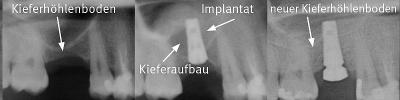

Schema: Ablauf Sinuslift:

Röntgenverlauf Sinuslift:

Der sogenannte Sinuslift ist ein operatives Verfahren, um den Oberkiefer im Bereich der Backenzähne zu erhöhen. Gerade in dieser Region gibt es verschiedene anatomische Variationen und häufig auch Situationen nach Zahnverlusten, bei denen der Kiefer stark reduziert ist und das Implantatlager aufzubauen ist.

Im Eingriff wird zunächst die Kieferhöhlenschleimhaut vorsichtig vom Knochen abgelöst und angehoben und dann das Aufbaumaterial der Wahl eingebracht. Dies lässt sich in örtlicher Betäubung, Sedierung oder Vollnarkose durchführen. Es treten weniger Schmerzen auf als bei einer Zahnentfernung, jedoch können die Schwellungen ausgeprägter sein. Die Komplikationen sind sehr gering und sehr selten.

Je nach individueller Situation wird das Implantat gleichzeitig oder nach einem Intervall von bis zu 6 Monaten in einem zweiten Eingriff gesetzt. Im Rahmen einer Diplomarbeit an der Universität Krems wurden unsere Erfolgsraten (= Implantaterhalt) untersucht. Bei Fällen, in denen Kieferaufbau und Implantatversorgung gleichzeitig erfolgten, lag die Erfolgsrate bei 96,7% über 10 Jahre. Es wurden insgesamt 477 Implantate ausgewertet. In 59 % der Fälle traten keinerlei Knochenverluste am Implantathals auf. Es waren auch keine Unterschiede bei geringen Restknochenhöhen feststellbar, so dass wir das Vorgehen in einem Eingriff auch bei Restknochenhöhen von weniger als 1 mm bevorzugen.